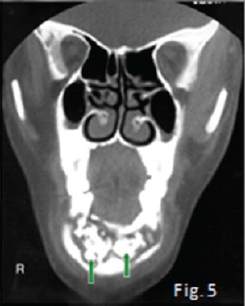

The cropped pantomograph (Fig 2) shows a "blurred/ fussy" appearance of the trabeculae due to loss of density. Signs of cortical destruction are also present. A provisional diagnosis of acute osteomyelitis was made which was confirmed histologically. Osteomyelitis is an inflammation of bone cortex and marrow that develops in the jaw usually after a chronic infection: No detectable radiographic features of the infection are discernible in the first 8-10 days (radiological principle: 30-60% decalcification before any changes are observed). About three weeks after the start of the infection irregular radiolucencies with enlargement of trabecular spaces are noticed (Fig 3). In the chronic stages, extensive areas of the bone may be destroyed and sequestra are formed showing the classic moth-eaten appearance and occasionally a pathological fracture may also be present (Fig. 4). Note the sequestration of bone in the anterior mandible on the coronal CT scan (Fig. 5) of another patient with chronic suppurative osteomyelitis The coronal T2 W. MRI scan (Fig. 6) shows the sequestrated bone (no signal black) is surrounded by zones of high signal intensity (white signal) representing the regions of active inflammation. Most cases of osteomyelitis of the jaw result from odontogenic infections, infections from a fracture site; or, rarely, haematogenous spread from a distant site, which is more common in the long bones. The cause of infection is most frequently Staphylococcus aureus, but haemolytic streptococci and Bacteroides are also encountered. The mandible is by far the most frequently affected; the adult maxilla is very seldom the site of osteomyelitis. The acute phase of suppurative osteomyelitis is sudden in onset and rapid in course. The patient experiences severe pain, fever, regional lymphadenopathy, and leucocytosis. Teeth in the region become loose and tender to percussion. When the mandible is involved there may be paraesthesia of the lower lip on the affected side. As soon as drainage is established, the pain eases, the temperature drops, the patient becomes more comfortable. Without treatment the infection may progress into a protracted chronic suppurative osteomyelitis. Differential diagnoses include malignancies and oteoradionecrosis.